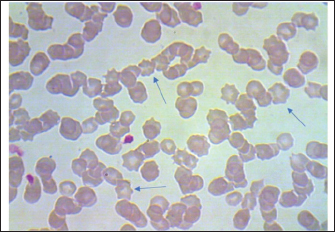

Fig. 1. Giemsa stain blood smear indicates equine RBCs infected with Mycoplasma haemofelis. 1000X.

Fig. 2. Blood smear indicates Mycoplasma haemofelis invades equine RBCs. Fluorescent microscopy,0.1% acridine orange staining. 1000X. qPCR resultIn the current study, 79%(79/100) of diseased horses were found to be positive using qPCR (Figs. 3 and 4). The agreement between the two diagnostic methods was analyzed using Cohen's Kappa statistic. The observed agreement was 91% (91/100), and the expected agreement by chance was 72.04%. The calculated Kappa coefficient was κ=0.678 (95% CI), indicating substantial agreement between cytological and qPCR diagnoses according to the Landis and Koch benchmark Table 1.